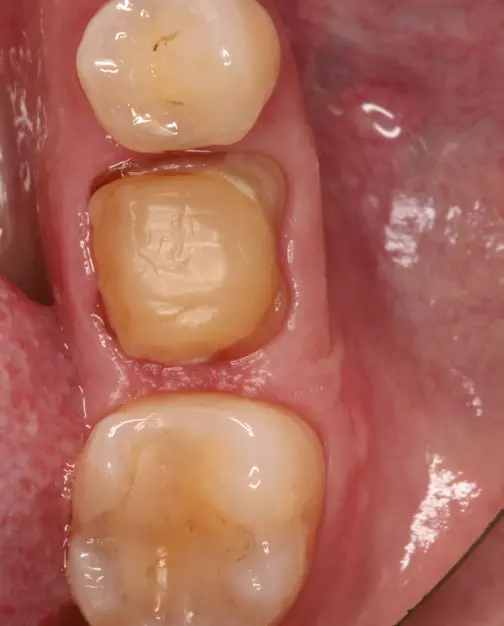

Sind, bei ausreichender Weichgewebshöhe, aufwendigere chirurgische Maßnahmen zur mittigen Implantatpositionierung erstrebenswert (Abb. 5), kann diese bei niedriger Weichgewebshöhe zu einem ungünstig großen Emergenzwinkel wie in Abbildung 4 führen.

30°).“ class=“wp-image-26386″/>